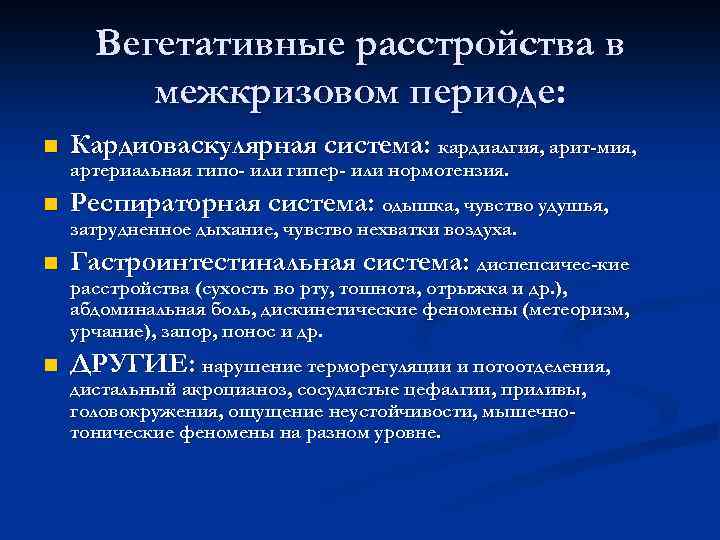

Вегетативные расстройства в межкризовом периоде: n Кардиоваскулярная система: кардиалгия, арит-мия, артериальная гипо- или гипер- или нормотензия. n Респираторная система: одышка, чувство удушья, затрудненное дыхание, чувство нехватки воздуха. n Гастроинтестинальная система: диспепсичес-кие расстройства (сухость во рту, тошнота, отрыжка и др. ), абдоминальная боль, дискинетические феномены (метеоризм, урчание), запор, понос и др. n ДРУГИЕ: нарушение терморегуляции и потоотделения, дистальный акроцианоз, сосудистые цефалгии, приливы, головокружения, ощущение неустойчивости, мышечнотонические феномены на разном уровне.